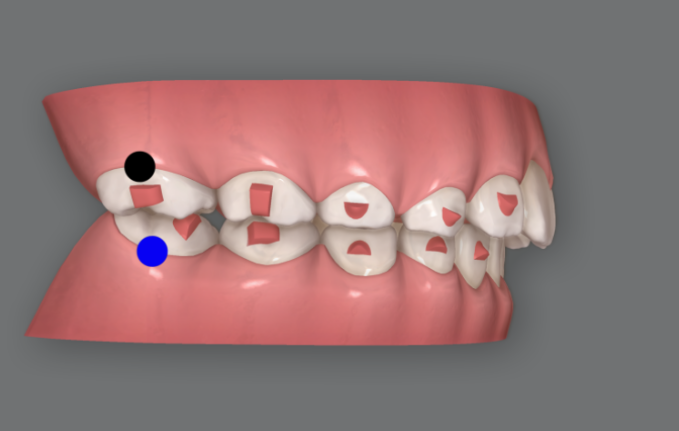

인비절라인 퍼스트 무턱 치료에 유용하게 사용하는 MA 라는 기능이 있습니다.

기존 액티베이터, 프랑켈, 바이오네이터 등 턱 위치와 성장을 조절하는 악정형 장치의 역할을 하는 기능을 합니다.

원리는 인비절라인 투명장치에 Wing 이라고 부르는 부분이 생기며 이 부분이 엇갈려서 물리면서 턱의 위치를 정위치로 유도하는 기능입니다.

효과는 기존 악정형장치보다 떨어지지 않고 오히려 아래 앞니 뻗침 등의 치아부작용이 적어서 무턱이나 비대칭 치료에 많이 사용합니다.

통상 악궁확장, 앞니배열, 과개교합 개선 등을 먼저 완료한 뒤에 치료 중간 MA 단계를 시작합니다.

26단계부터 57단계 까지는 아래턱의 위치를 유도하는 MA 단계이고 장치모습을 보면 파란색으로 표기된 <윙>이 위아래 각각 두쌍씩 튀어나와 있는 것이 보입니다.